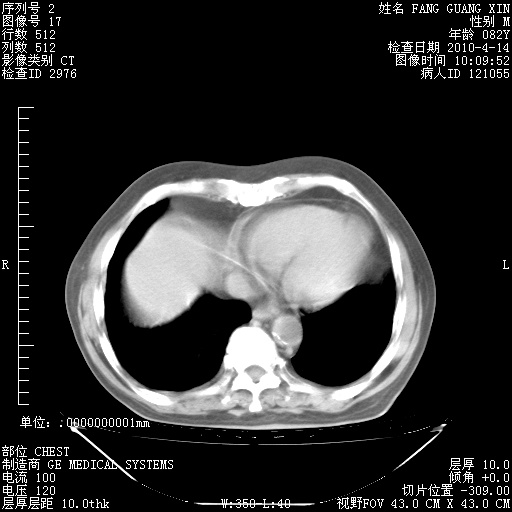

肺部CT平扫未见异常。